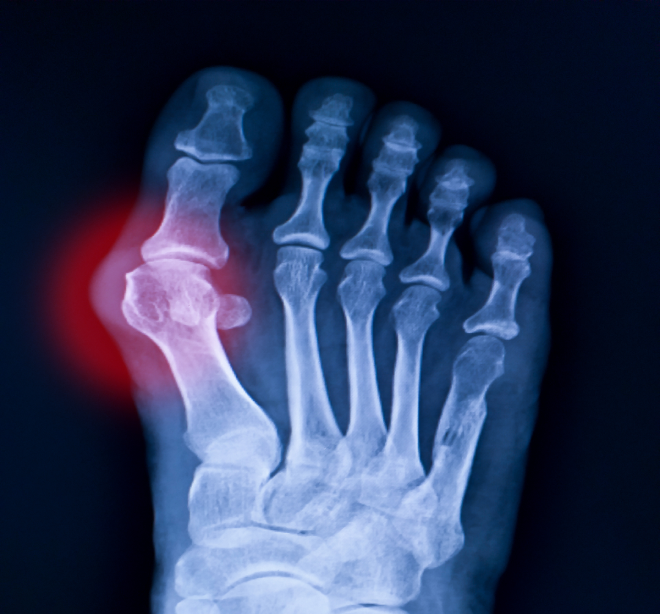

Infiltraciones articulares o periarticulares

Aplicación de infiltraciones para aliviar el dolor según la patología del paciente.